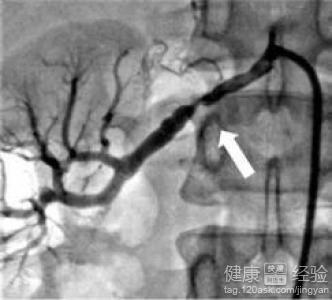

2而患者在進行治療的時候一定要弄清楚自身究竟是由於什麼樣的腎部疾病從而導致自己的腎性高血壓的,主要的疾病有:腎動脈內膜粥樣硬化瘢塊、腎動脈纖維組織增生等一些其他疾病。

3除此之外其他的病因就是腎動脈受壓迫,這個因素也是比較嚴重的,大部分的時候都是由於腹主動脈瘤、腫瘤、囊腫等一些腫瘤類型的疾病導致的,病情相對來說也會比較嚴重一些的。